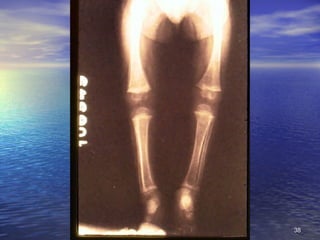

2. Signos Circunstanciales No se encuentran siempre, sino que están condicionados a causas ambientales o ecológicas, no específicas: alteraciones de la piel y faneras, lesiones oculares, de lengua, óseas, de músculos y ligamentos, de aparato digestivo, alteraciones hematológicas, neurológicas, edema

2. Signos CircunstancialesNo se encuentran siempre, sino que están condicionados a causas ambientales o ecológicas, no específicas: alteraciones de la piel y faneras, lesiones oculares, de lengua, óseas, de músculos y ligamentos, de aparato digestivo, alteraciones hematológicas, neurológicas, edema